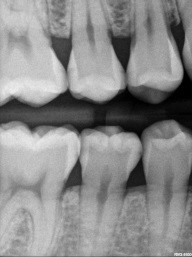

Patient 3: Tooth #12

This is a tough one for clinicians to believe, but the distal of #12 does, in fact, have caries! It appears less obvious and short of the DEJ. The photo mid-prep shows otherwise. Premolars, especially, are frail to begin with. Keeping any and all restorations conservative is the name of the game.